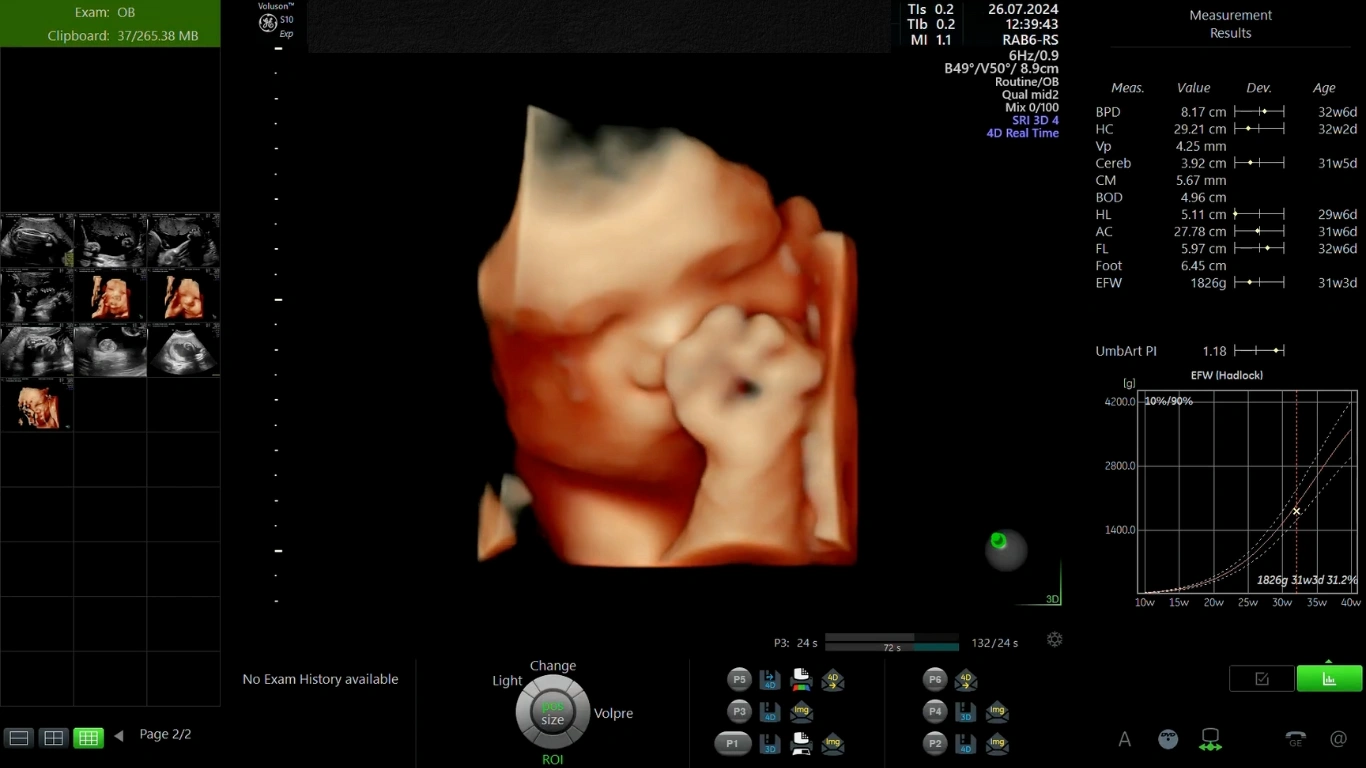

Câu hỏi thai nhi 32 tuần nặng bao nhiêu là mối quan tâm hàng đầu của mọi mẹ bầu. Cân nặng ước tính (EFW) được tính toán qua siêu âm phụ thuộc vào sự tăng trưởng riêng biệt của mỗi bé. Bảng cân nặng chuẩn của thai nhi theo WHO chỉ là khoảng tham chiếu tương đối.

Theo dữ liệu tiêu chuẩn của Tổ chức Y tế Thế giới (WHO), mốc thai 32 tuần 0 ngày cân nặng đạt:

Thông qua siêu âm, các thông số sinh trắc học được sử dụng để ước tính cân nặng thai nhi. Đây là các chỉ số thai nhi 32 tuần quan trọng mà mẹ thường thấy trong phiếu siêu âm :